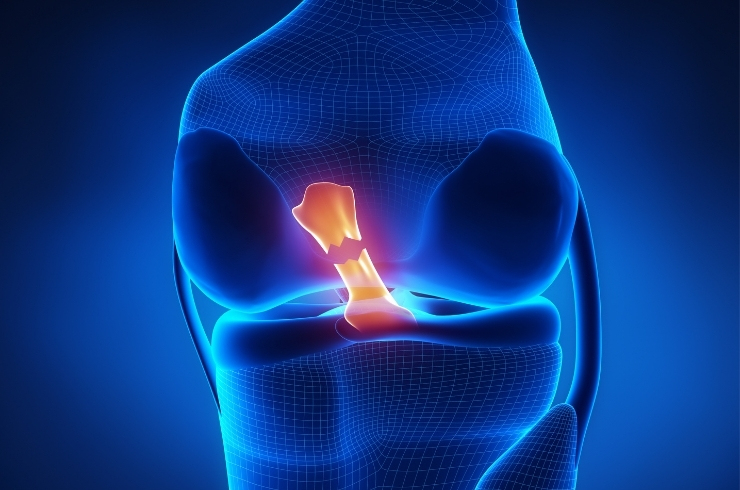

Minimally invasive knee procedures to repair ligaments, restore stability, reduce pain, and enable faster functional recovery.

Advanced techniques to repair meniscus and preserve cartilage, preventing degeneration and maintaining long-term joint health.

Expert evaluation and treatment for knee pain and sports injuries, ensuring faster recovery and safe return to activities.

Minimally invasive treatment for sports injuries, ensuring faster recovery, reduced pain, and improved joint function outcomes effectively.